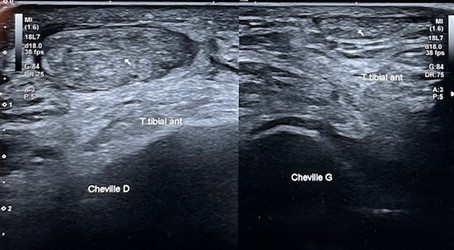

Echographie de la face antérieure de la cheville

Rupture du tendon du muscle tibial antérieur droit : épaississement du tendon , moignon rétracté (cheville droite)

Vacuité de la gaine : rupture du tendon avec moignon ascensionné et non visible en coupe distale du tendon